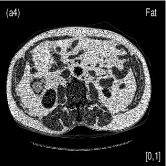

We also evaluated the proposed PWLS-TNV- method using clinical pelvis data. The patient’s pelvis data was acquired by Siemens SOMATOM Definition flash CT scanner using DECT imaging protocol. Table 4 lists acquisition parameters in the pelvis data scan. Fig. 5 shows the high- and low-energy CT images of the pelvis data. Fig.5 (b) shows selected basis materials, bone, iodine, muscle, fat and air, and their assosicated ROIs highlightened in white dashed line circles. We implemented the Direct Inversion method in mendonca2014a and used its results as the initialization for the PWLS-EP-LOOP xue2017statistical and the proposed PWLS-TNV- method. Fig. 6 shows the decomposed material images by the Direct Inversion, the PWLS-EP-LOOP and the PWLS-TNV- method. Table 5 summarizes the means and noise STDs of the decomposed material images by the above three methods. The volume fraction (VF) accuracies are , , and for the Direct Inversion method, the PWLS-EP-LOOP method and the proposed PWLS-TNV-, respectively. Compared with the Direct Inversion and PWLS-EP-LOOP method, the proposed method improves the VF accuracy by and respectively. The proposed PWLS-TNV- method decomposes basis material images more accurately, suppresses noise and decreases crosstalk, while retaining spatial resolution of the decomposed images compared to the other two methods.